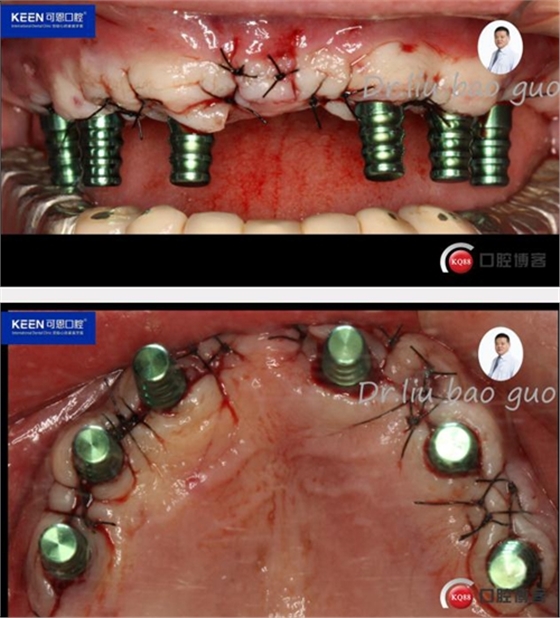

手術(shù)過程

(因設(shè)備限制,未能實(shí)現(xiàn)手術(shù)全程數(shù)字化導(dǎo)板,僅在手術(shù)之前導(dǎo)板定位)

術(shù)后照片